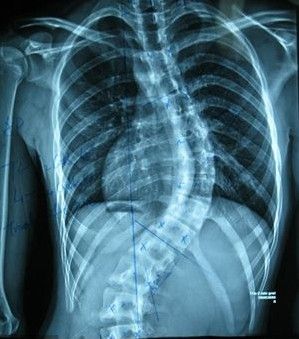

强直性脊柱炎病因为什么再度来临